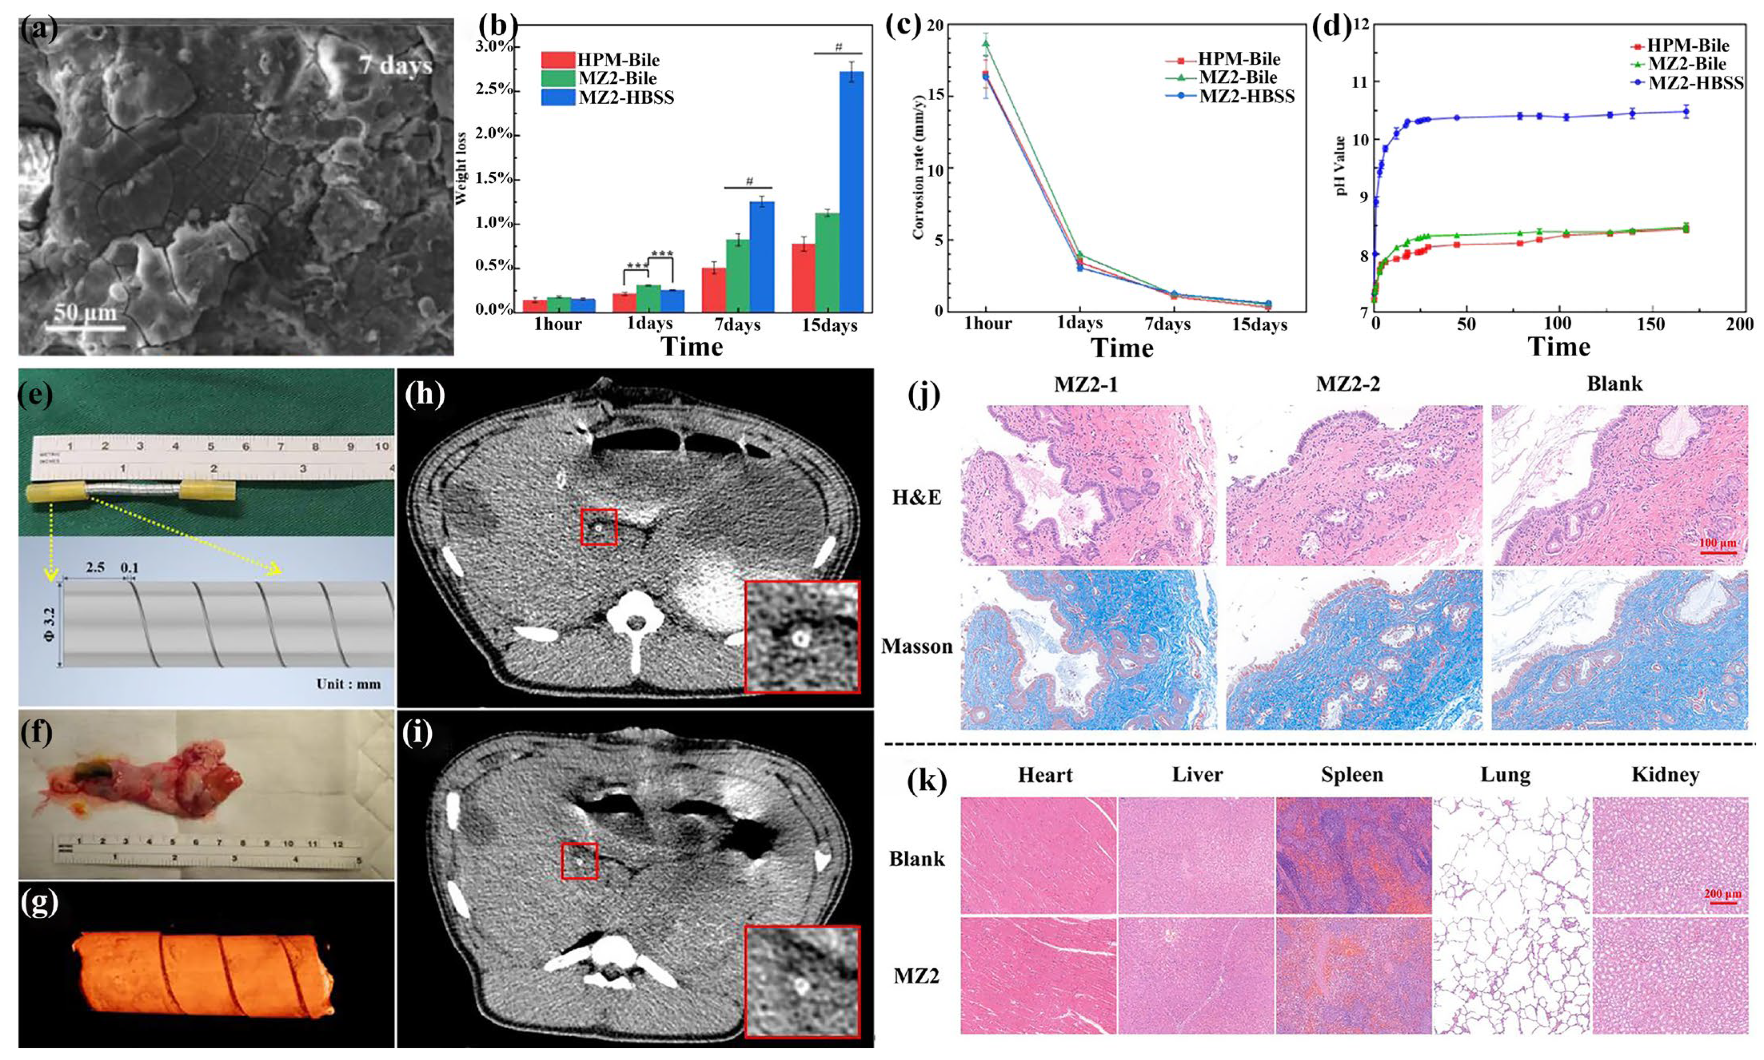

3.8. Biliary Stent